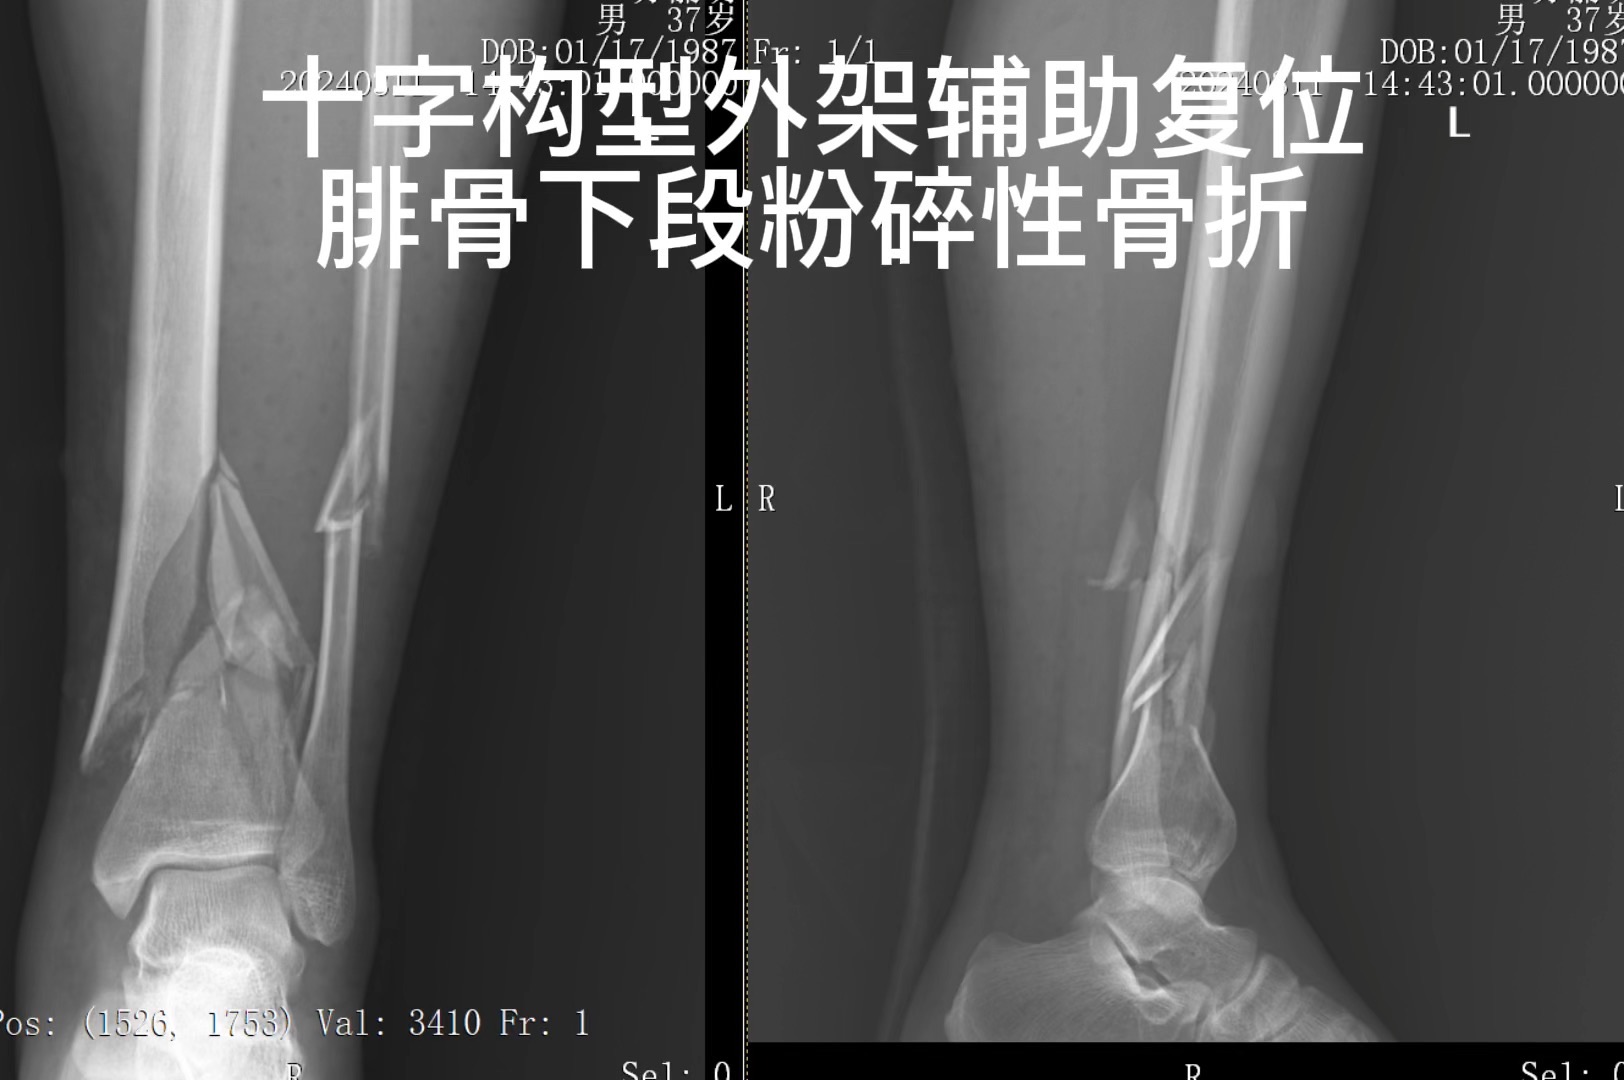

意见 患者目前下肢肿胀 麻木 水泡形成 被动活动足趾疼痛 筋膜间隙综合症诊断陈立 需要筋膜间隙切开 减压 胫骨骨折以十字型外架跨踝闭合复位 外固定 二期调整 或改内固定 腓骨切开复位 弹性髓内针固定。伤口负压吸引

手术名称:左胫骨粉碎性骨折切开复位外固定架固定术+腓骨下段骨折切开复位弹性髓内钉内固定术+左小腿骨筋膜间室综合征切开减压术+VSD负压引流术+左小腿后侧挫裂伤清创术

十字型外固定架跨踝辅助胫骨下段骨折闭合复位 外固定

以外架辅助 胫骨闭合复位 外固定

第一次手术效果较好 复查X线及CT见胫骨向内侧成角5度 略内旋 。